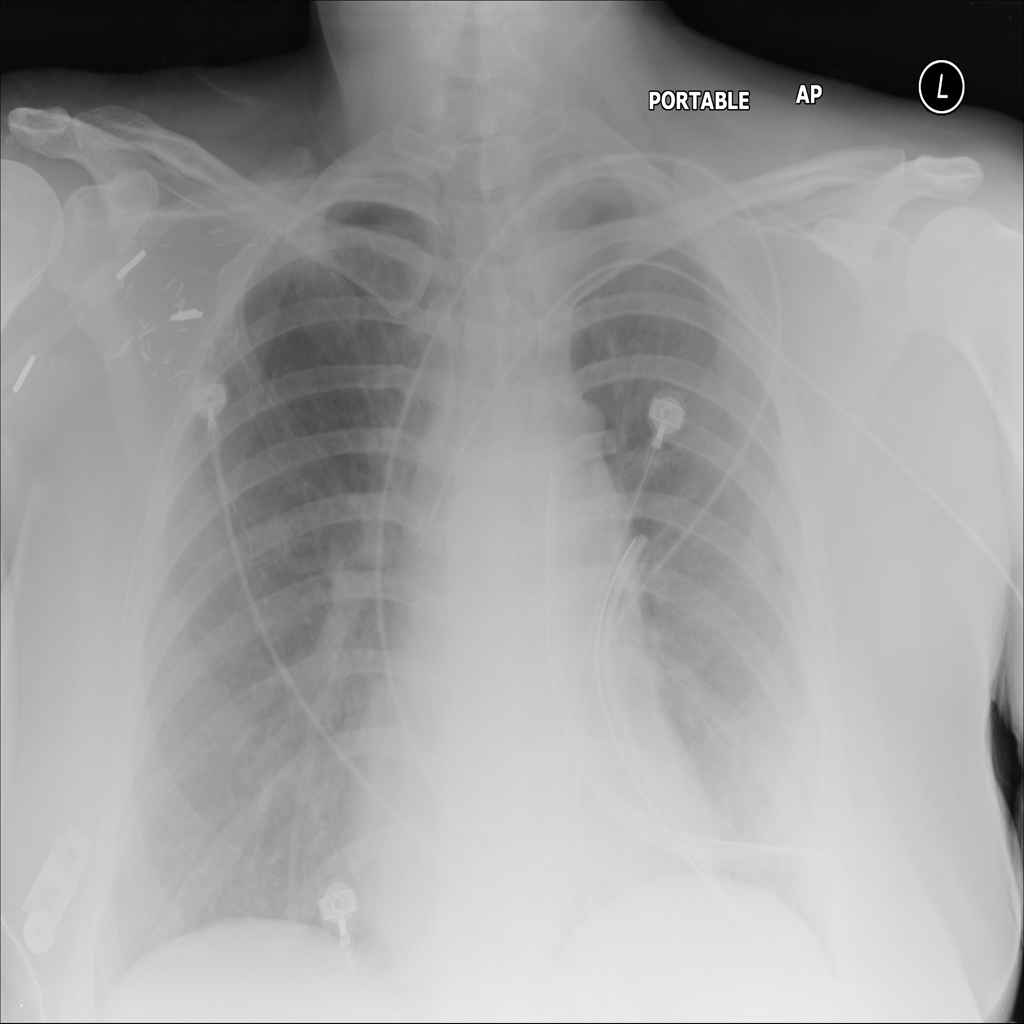

Mass

A mass is a larger focal opacity or lesion seen on the image. It is a descriptive finding that can have several causes and usually needs more imaging or clinical context to characterize.

PAT-D7A5 · IMG-000Mass

PAT-D7A5 · IMG-000

PA